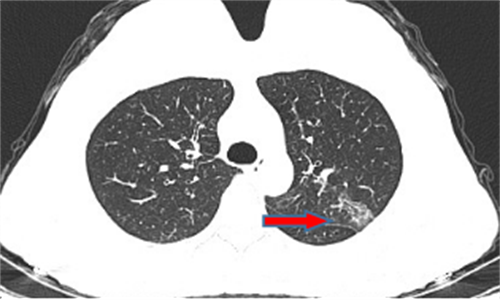

龙先生,65岁,体检发现右下肺结节,术后病理诊断肺结节为硬化性血管瘤。